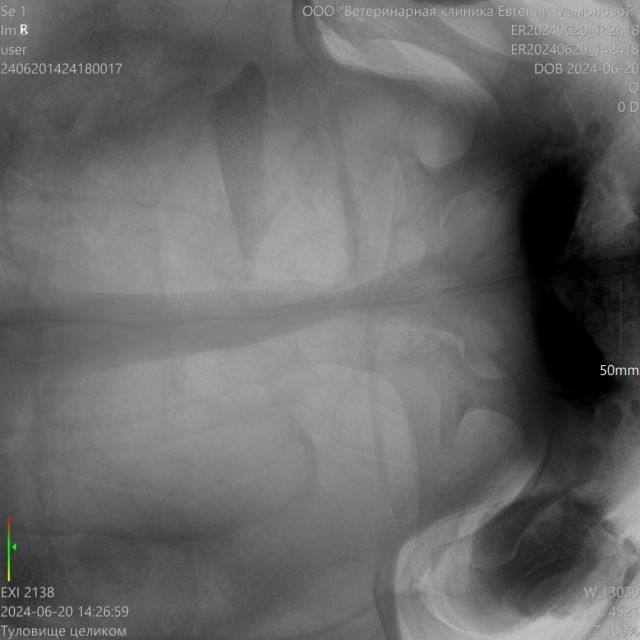

Кишечная непроходимость? большой шпороносной черепахи

Здравствуйте, ищем у кого есть опыт в операциях на кишечнике у больших черепах. Срочно нужна помощь в диагностики. Делали КТ, рентген с контрастом, кровь. Чёткого описания ни рентгена, ни КТ нет.

Проблема серьёзная. Кто поможет? ???